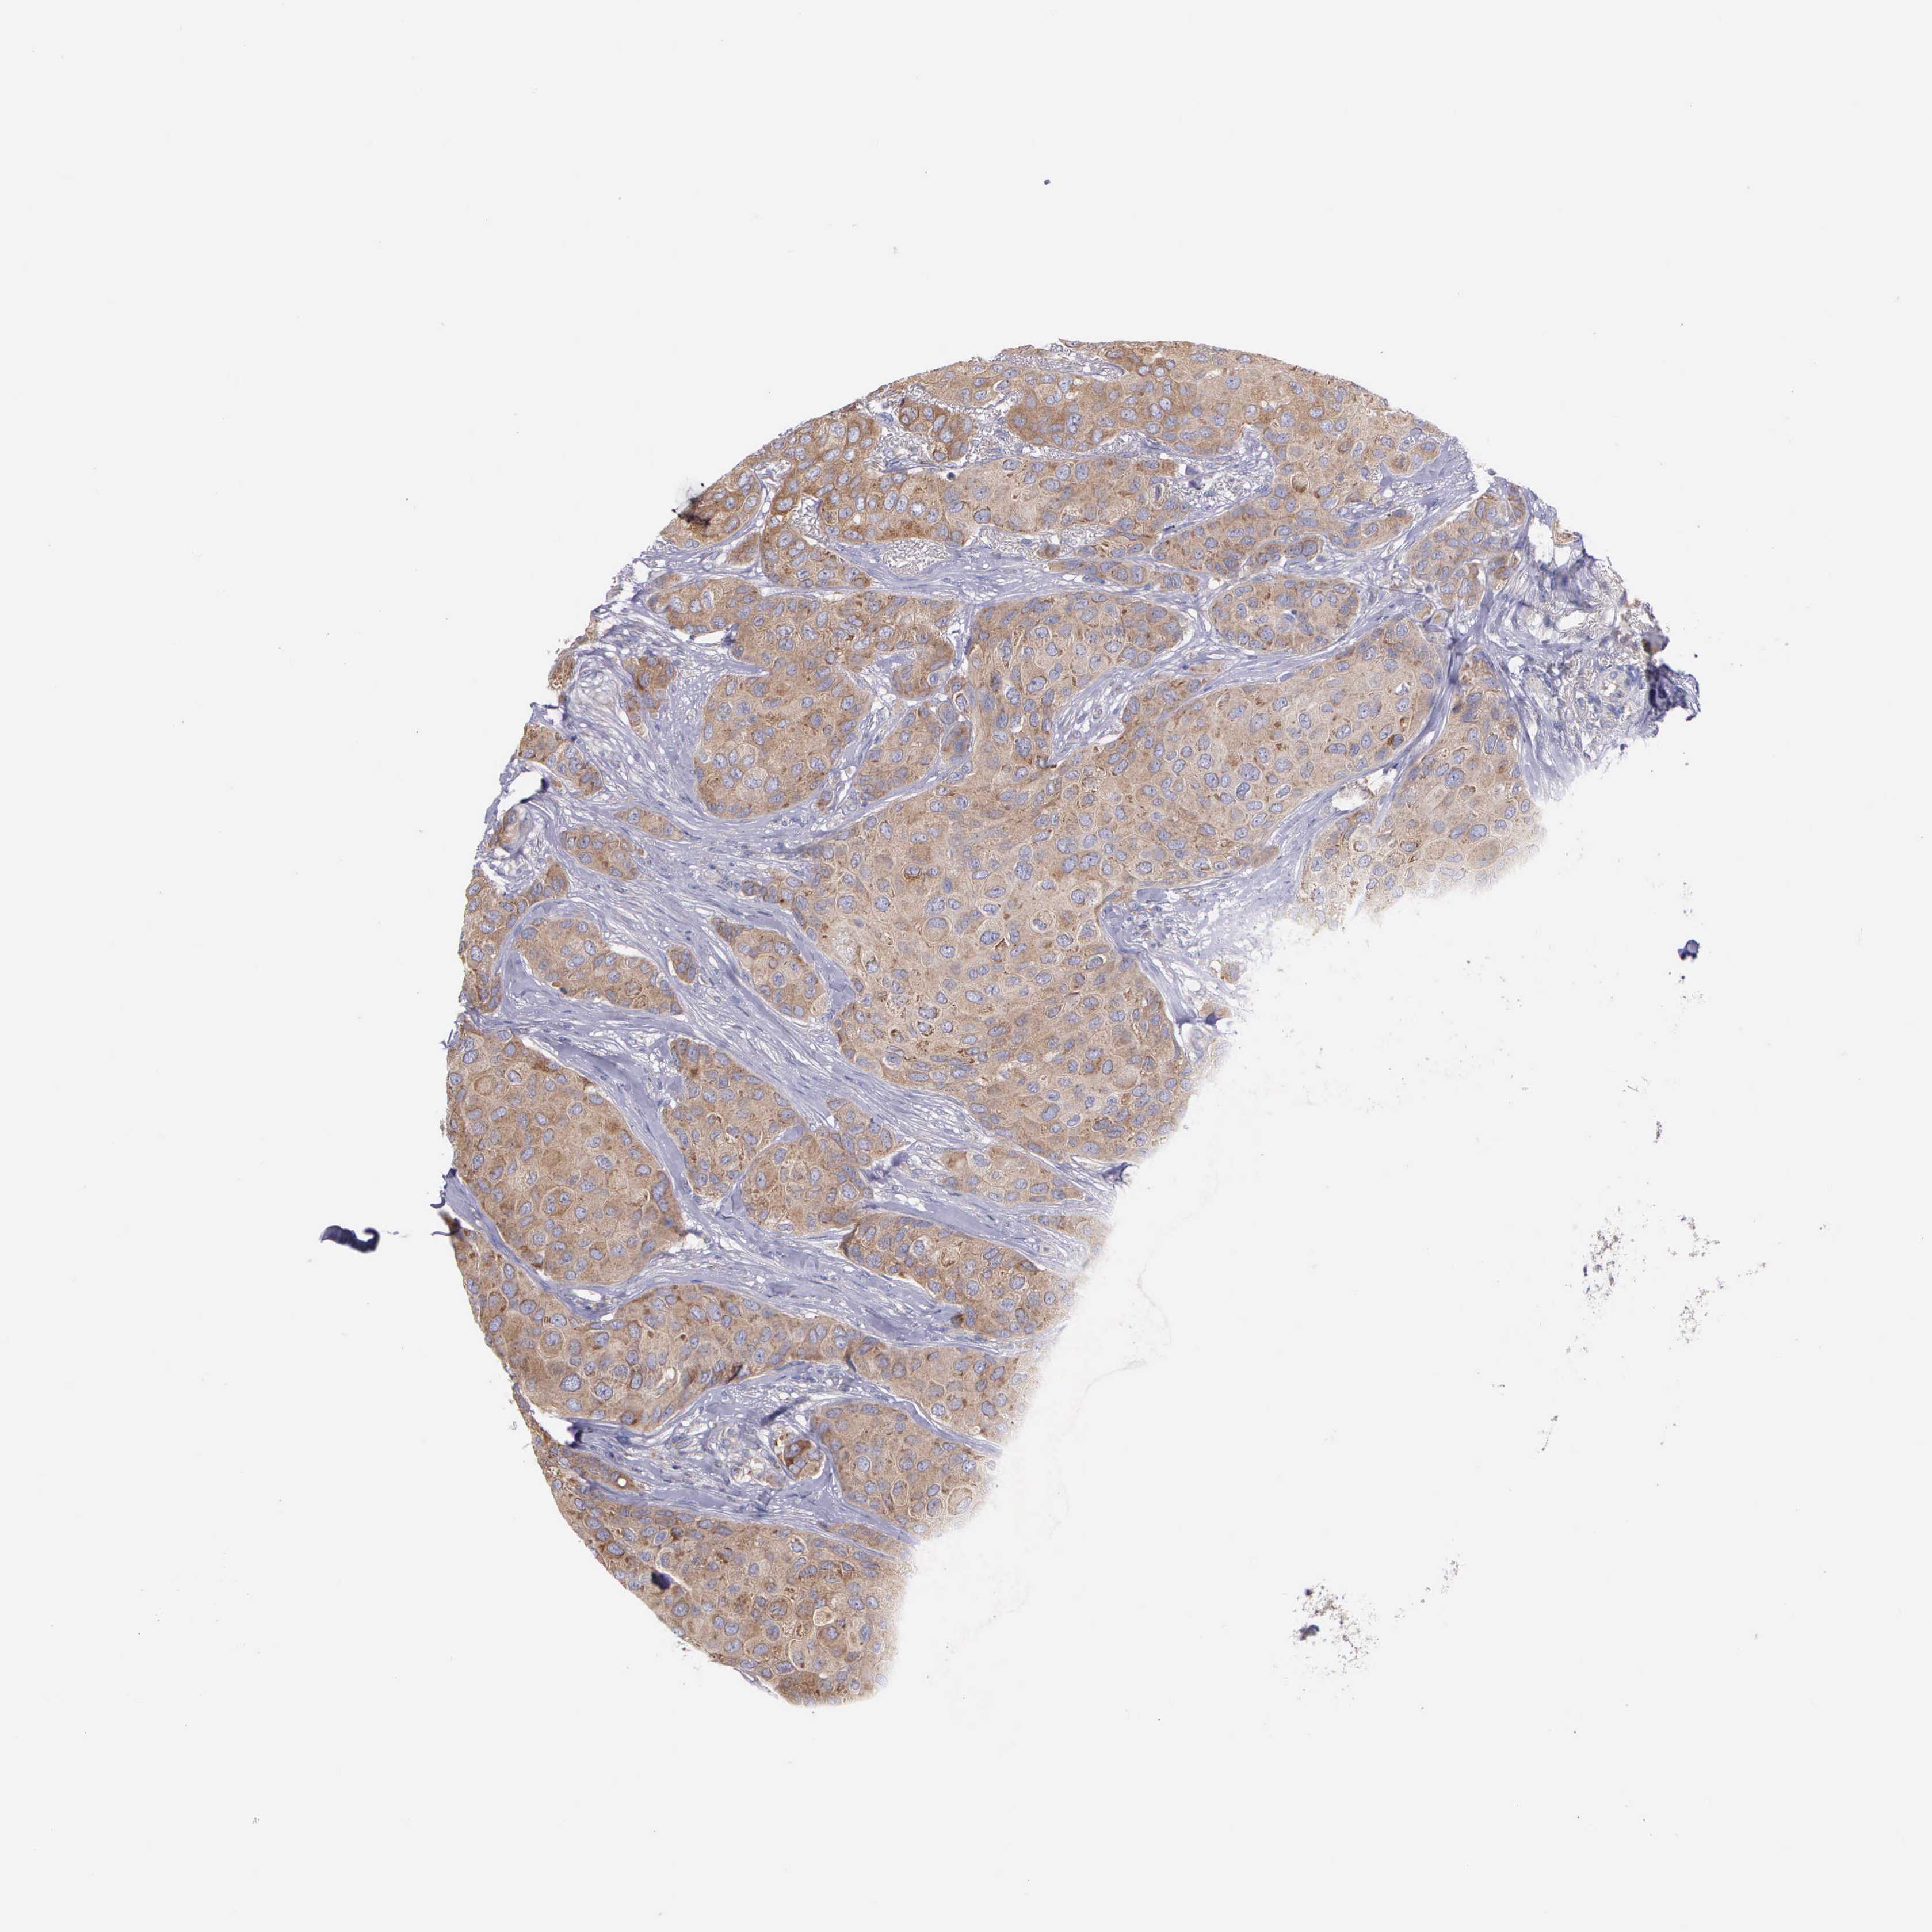

BREAST CANCER - Protein expressioni

A mouse-over function shows sample information and annotation data. Click on an image to view it in a full screen mode. Samples can be filtered based on level of antibody staining by selecting one or several of the following categories: high, medium, low and not detected. The assay and annotation is described here.

Note that samples used for immunohistochemistry by the Human Protein Atlas do not correspond to samples in the TCGA dataset.

Antibody stainingi

Antibody staining in the annotated cell types in the current human tissue is reported as not detected, low, medium, or high, based on conventional immunohistochemistry profiling in selected tissues. This score is based on the combination of the staining intensity and fraction of stained cells.

Each image is clickable and will lead to virtual microscopy that enables deeper exploration of all samples and also displays staining intensity scores, fraction scores and subcellular localization as well as patient and tissue information for each sample.

Antibody HPA000387

Antibody HPA000922

Staining

High

Medium

Low

Not detected

Intensity

Strong

Moderate

Weak

Negative

Quantity

>75%

75%-25%

<25%

None

Location

Nuclear

Cytoplasmic/membranous

Cytoplasmic/membranous,nuclear

Duct carcinoma

Lobular carcinoma

Neoplasm, malignant, NOS